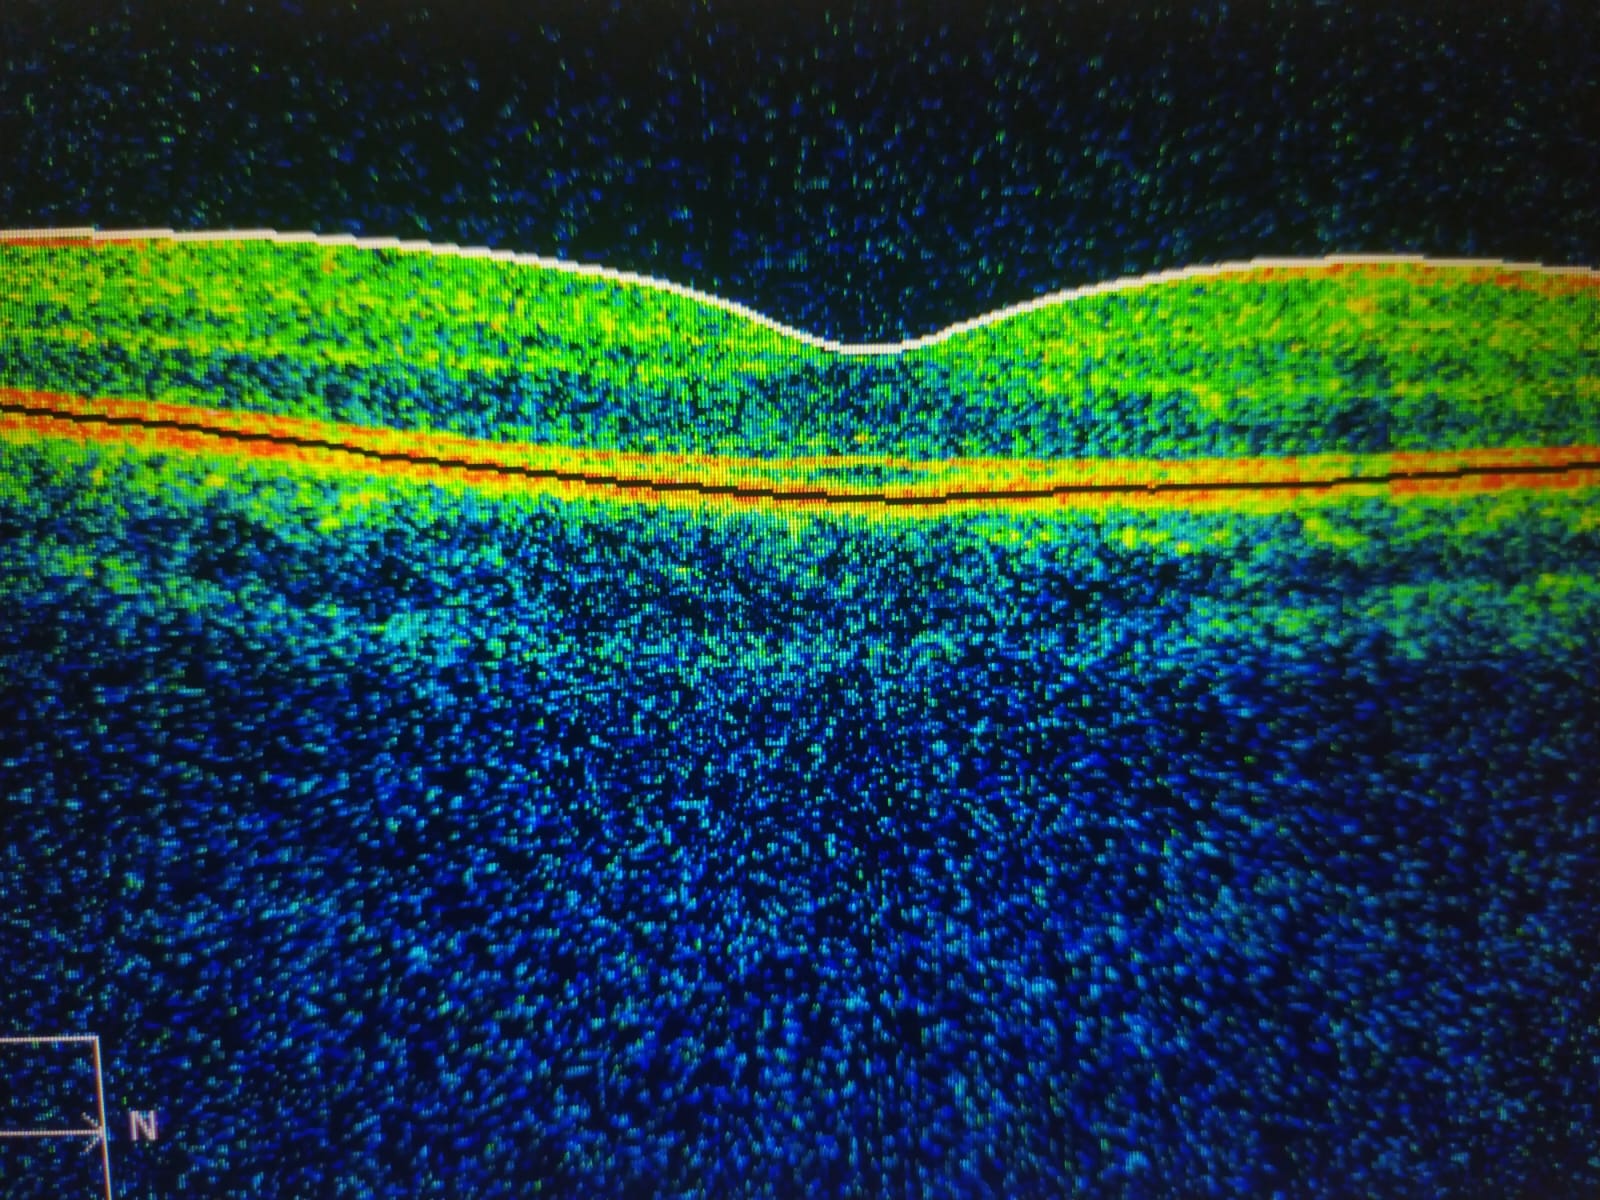

El cubo macular es una adquisición de miles de cortes de la retina en una zona específica: la mácula, el área central de la visión.

Al unirlos digitalmente, se genera un volumen 3D de la retina, que puede observarse en diferentes planos y con gran detalle.

📊 Así, el cubo no solo muestra una línea de la mácula (como el clásico B-scan), sino que ofrece un mapa completo que podemos explorar capa por capa.